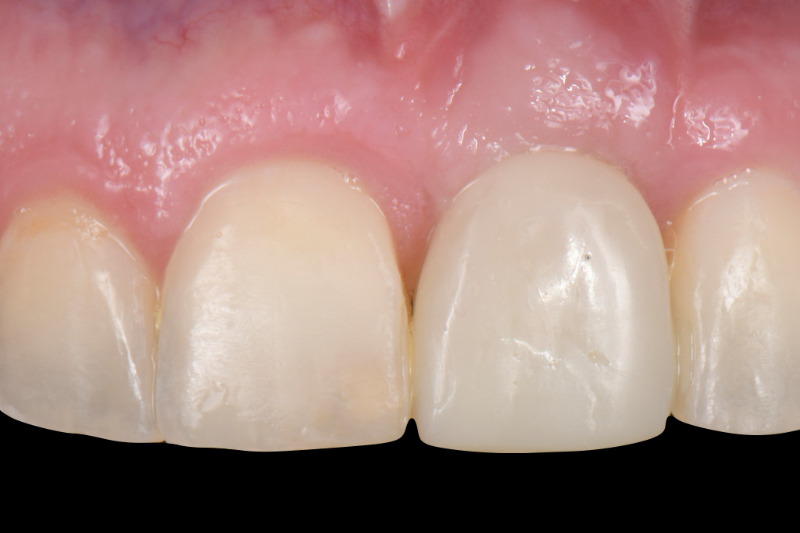

The esthetic success of an anterior implant-supported restoration mostly depends on having a soft-tissue architecture indistinguishable from the adjacent teeth. One of the most critical steps to achieve this “esthetic success” is correctly using the provisional restoration to optimize and properly contour (groom) the peri-implant tissue anatomy.

Once the optimal emergence profile has been developed, we need to communicate and transfer this information properly to the laboratory. Unfortunately, all implant companies provide stock round impression copings that do not precisely transfer the soft-tissue contours. A simple protocol to communicate this information is described here.

This visual essay walks through a step-by-step description of how to fabricate a personalized impression coping with transfer ofthe peri-implant tissue anatomy properly.